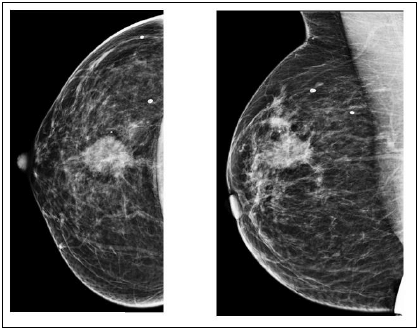

Paciente, 45 anos, encaminhada à mamografia por nódulo palpável em exame físico. Não há exames prévios.

Tal lesão deve ser classificada como BIRADS: